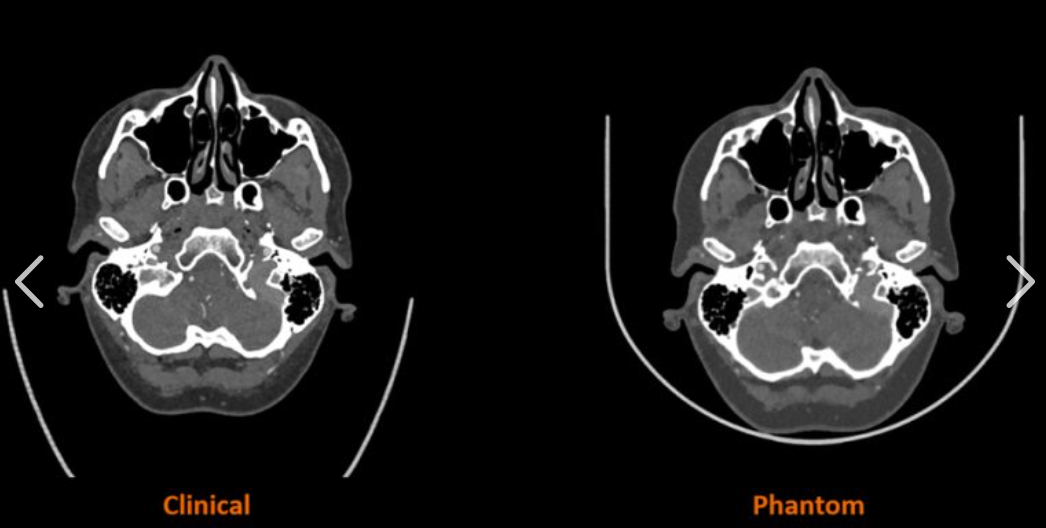

同步辐射硬X射线纳米分辨CT成像具有高空间分辨的三维成像能力,可以在亚细胞尺度直接

观察自组装纳米颗粒的三维空间分布行为,对纳米药物研发及探究其药理、毒理学性质具有重要意

同步辐射硬X射线纳米分辨CT成像

一种先进的成像技术,重建出物体内部的三维结构图像,用于观察细胞内部的精细结构,如

细胞器的形态和分布;研究生物大分子的组装结构和动态变化;追踪纳米药物在细胞和生物体内的

分布、代谢过程等,为生命科学研究提供了重要的技术支持。

成像与数据采集

DL - HXT 成像参数设置:根据细胞和纳米颗粒的特点,调整 DL - HXT 技术的成像参数,如 X 射线的能量、剂量、扫描速度、分辨率等。确保成像参数能够提供足够的对比度和分辨率,以便清晰地观察纳米颗粒和细胞器的形态和分布。